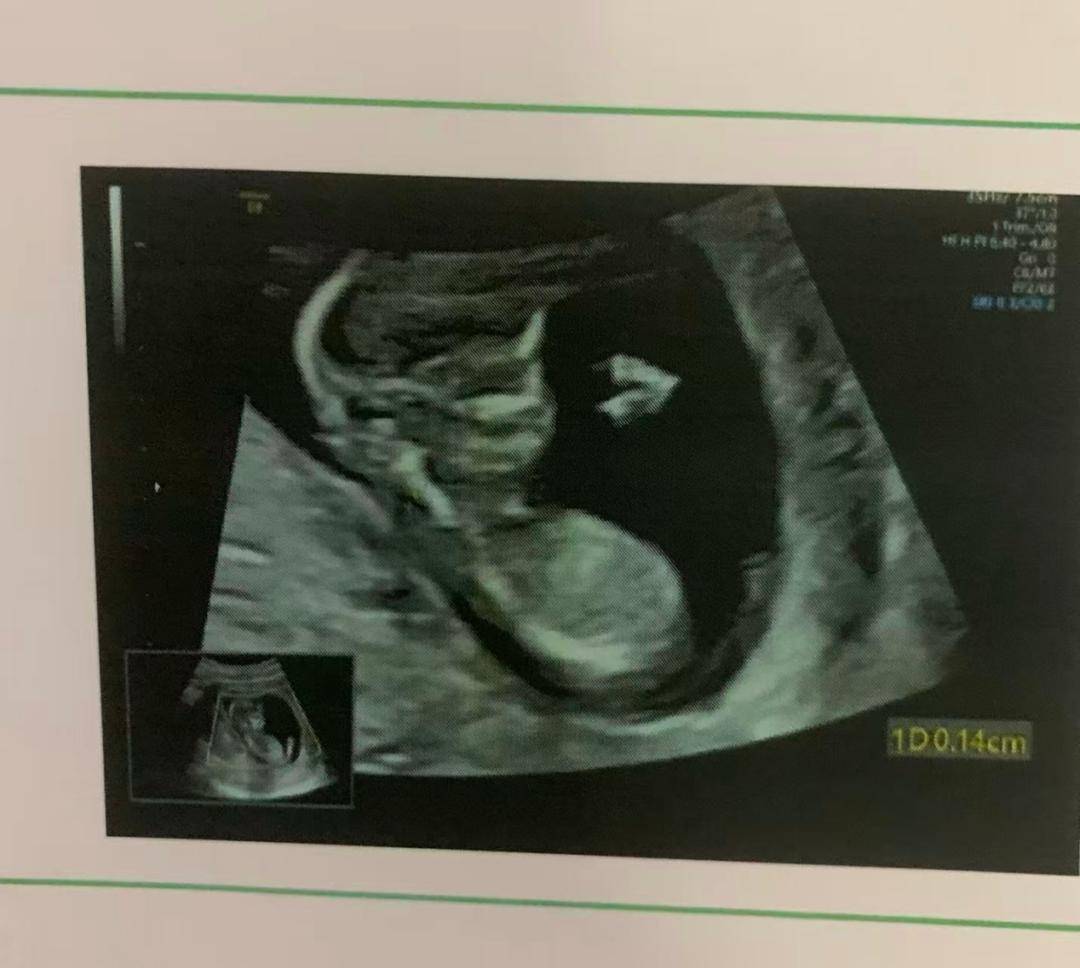

转折出现在八月。孕反终于好转,肚子也渐渐隆起。有一天去做四维B超,屏幕上出现了那个婴儿的小小身影——圆圆的脑袋、圆圆的肚子。医生笑着指给她看:“TA在动呢。”邓思蓉的眼泪瞬间涌了出来,“好可爱呀。”

邓思蓉在B超中看到孩子

那一刻,她的心被彻底融化,彻底接受了即将成为母亲的现实。